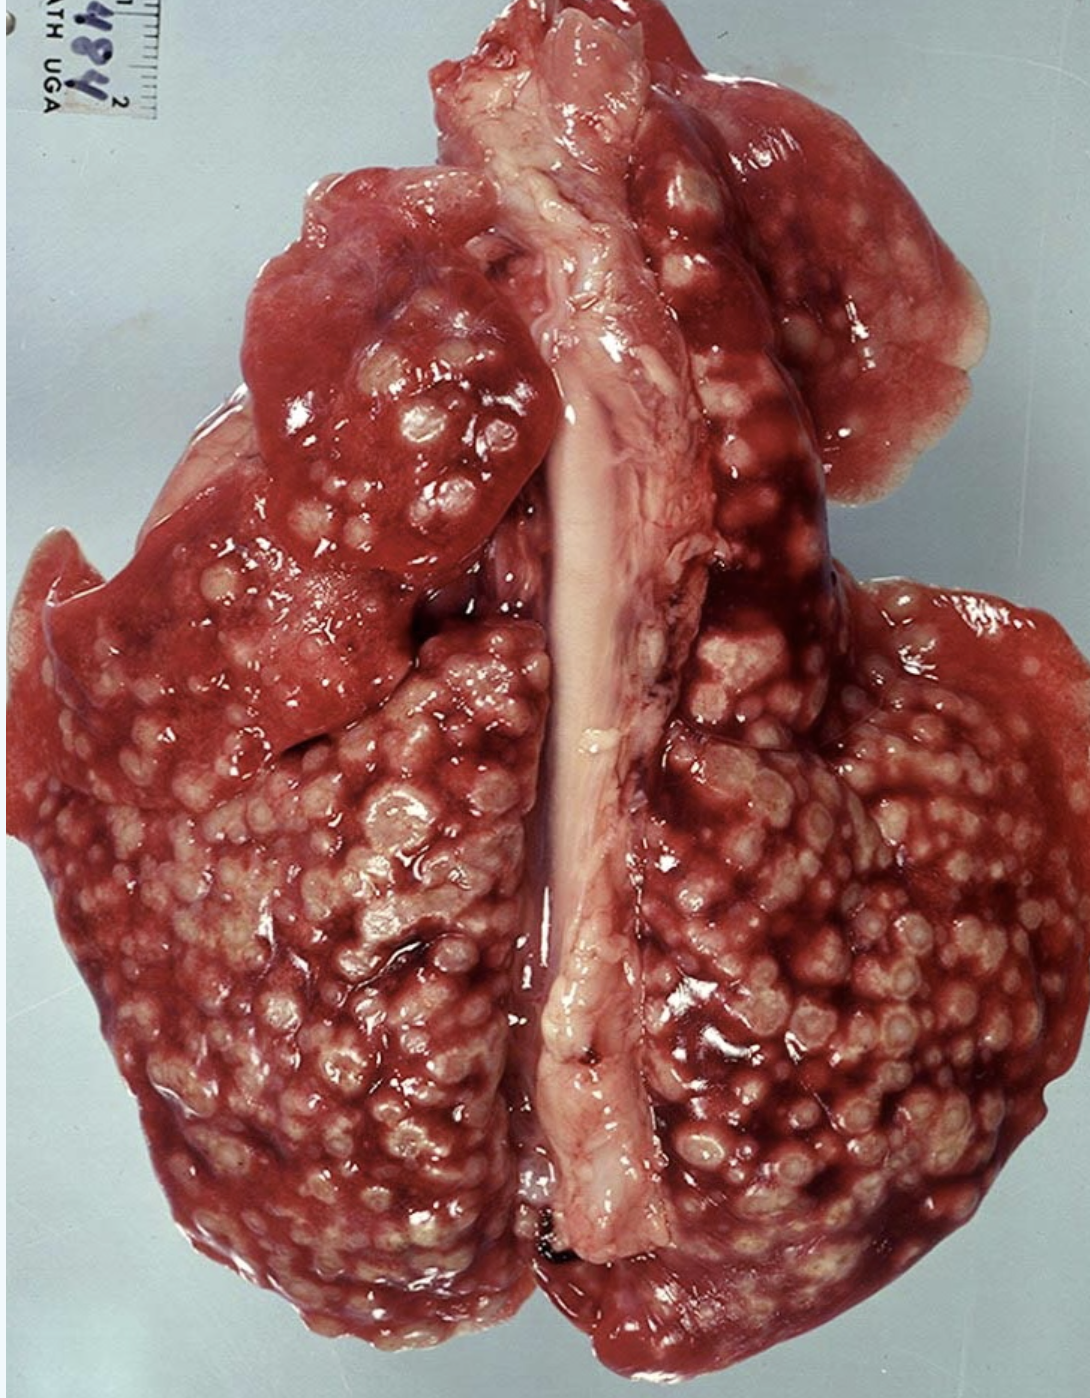

What is the most likely diagnosis?

a.Pre-neoplastic hyperplasia

b.Pulmonary adenoma

c.Pulmonary metastases

d.Pre-neoplastic dysplasia

A

Pulmonary metastases